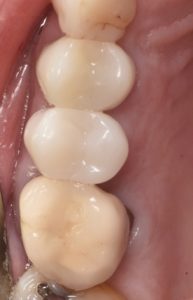

This video demonstrates a fully guided immediate implant placement protocol following premolar extraction, combined with immediate provisional restoration. The case highlights a digitally driven workflow designed to enhance accuracy, efficiency, and prosthetically guided implant positioning.

Step-by-step, the procedure covers atraumatic tooth extraction, guided implant placement using a surgical guide, and chairside fabrication and delivery of an immediate provisional restoration. Clinical considerations for achieving primary stability, soft tissue preservation, and optimal emergence profile are emphasized to support predictable esthetic and functional outcomes.

- Principles of immediate provisionalization and emergence profile development